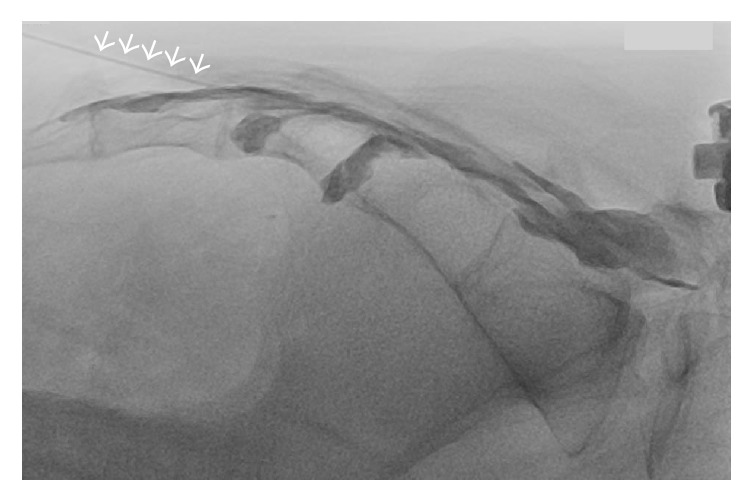

7. Contrast injection: Inject under lateral real-time fluoroscopy, then AP view to assess laterality and cephalad flow. Confirm absence of vascular uptake or excessive flow through ventral sacral foramina.

Catheter Placement Option (per IPSIS)

When more targeted delivery is desired with lower volumes:

• A catheter is inserted through a non-shearing introducer needle (polished Coude or Tuohy)

• The catheter is observed ascending the caudal epidural space under lateral fluoroscopy

• The catheter may be steered toward the symptomatic side by rotating it

• When a catheter is used, the volume of injectate should be reduced to maintain high medication concentration at the target